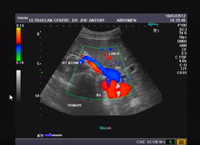

Ecodoppler Colorido de Artérias Renais

• from DR. JOE A

• Fevereiro, 2012

Demonstração de exame de artérias renais